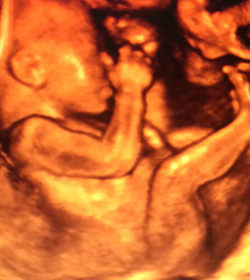

3D Live Ultrasound

3D & 4D Live Ultrasound in Tarzana, Encino, Van Nuys, Northridge, & Reseda

With 3D Live Ultrasound technology you can see the motion of the baby (3D Live / 4D are the same technology). Some companies call it 3D Live and some call it 4D. If your baby has a large, clear pocket of amniotic fluid around the face, is moving about and is developed enough, then we can get great clips of motion (3D live or 4D Effects). The 3D Live/ 4D effect clips are typically only a few minutes.

Most 3D/4D ultrasounds are done between 24 and 34 weeks. Prior to 24 weeks, babies have not started putting on brown fat so they won’t have the “Gerber Baby” look. Around 27 to 28 weeks is usually considered the ideal time, because the baby does have some fat and still has plenty of room to move. After 34 weeks, the baby begins to get a little squished and may be facing the spine, which is the position for birth.

First of all, you’ll enjoy the viewing experience more if your baby has room to move around. Often you can watch little hands and feet in motion, toes and fingers wiggling, and see your baby’s face from all different angles. Second, if the baby is in a position that makes viewing difficult (facing the spine or covering its face with hands and feet), you have a better chance of repositioning your baby if there’s room for it to move.